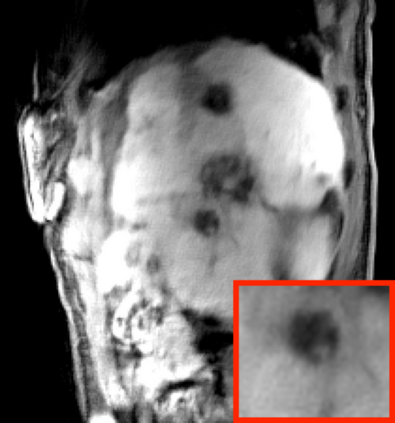

Deep neural networks for medical image reconstruction are traditionally trained using high-quality ground-truth images as training targets. Recent work onNoise2Noise (N2N) has shown the potential of using multiple noisy measurements of the same object as an alternative to having a ground truth. However, existing N2N-based methods cannot exploit information from various motion states, limiting their ability to learn on moving objects. This paper addresses this issue by proposing a novel motion-compensated deep image reconstruction (MoDIR) method that can use information from several unregistered and noisy measurements for training. MoDIR deals with object motion by including a deep registration module jointly trained with the deep reconstruction network without any ground-truth supervision. We validate MoDIR on both simulated and experimentally collected magnetic resonance imaging (MRI) data and show that it significantly improves imaging quality.

翻译:用于医学图像重建的深神经网络传统上是用高质量的地面真实图像作为培训目标来培训的。最近关于噪音2噪声(N2N)的工作表明,有可能使用同一物体的多重噪音测量来替代地面真相;然而,现有的N2N方法不能利用来自各种运动状态的信息,限制了它们了解移动物体的能力。本文件通过提出一个新的运动补偿深度图像重建(MoDIR)方法来解决这一问题,该方法可以使用来自若干未登记和吵闹的测量数据的信息进行培训。MDIR处理物体运动问题的方式是,在没有地面真相监督的情况下,与深层重建网络共同培训一个深层登记模块。我们在模拟和实验收集的磁共振成像(MRI)数据上验证了MDIR,并表明它大大提高了成像质量。